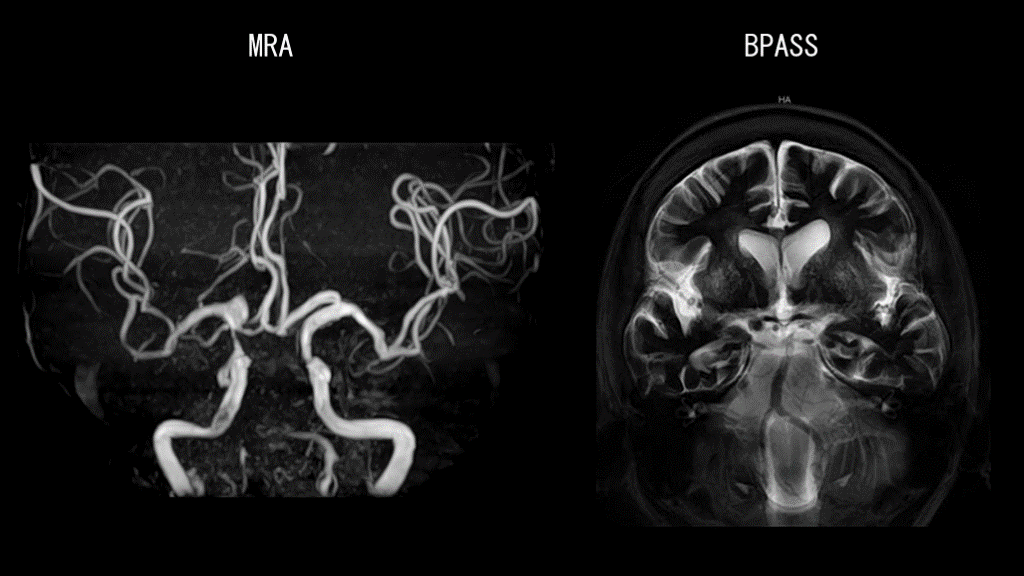

MRA BPASS

#14.

症例1 アテローム血栓性脳梗塞(A to A embolism) ・梗塞巣が多発している ・梗塞範囲が小さい ・動脈硬化のリスクがある ・口径不整を多数認める 狭窄した椎骨動脈、脳底動脈で作られた 血栓が断片化し小梗塞が多発した

#15.